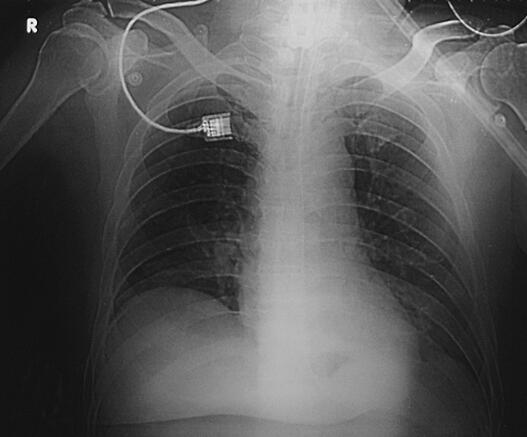

图1 CT(2月7日)结果:双下肺肺不张,双侧胸腔积液

诊治经过:患者入笔者科室后一般情况较差,血压测不出,氧饱和度84%,予以羟乙基淀粉扩容,多巴胺、去甲肾上腺素微泵维持血压,碳酸氢钠纠正酸中毒。立即予以气管插管,呼吸机辅助通气。完善相关检查:CT(图1)结果:①头颅CT平扫未见明显异常;②双下肺肺不张;③双侧胸腔积液;④肝右叶钙化灶。血常规(2月7日):WBC 20.9×109/L,N 94%。心脏彩超(2月8日):左心室舒张末内径61mm,射血分数38%。胸片(图2~图4)诊断:①双侧肺炎;②颈椎术后。先后给予头孢曲松钠和左氧氟沙星、美罗培南和替考拉宁抗感染。因痰培养鲍曼不动杆菌(2月10日),对头孢哌酮-舒巴坦钠敏感,余均耐药,故停用美罗培南,改用头孢哌酮-舒巴坦钠。多次血培养结果提示白念珠菌(2月6日、2月7日、2月9日、2月10日),对氟康唑和伊曲康唑均敏感,因为患者肌酐高,肾功能异常,故给予米卡芬净和氟康唑抗真菌治疗。患者血糖高,2月6日末梢血血糖33.1mmol/L,给予胰岛素强化治疗,但是血糖控制不佳,一直在11mmol/L以上。同时给予化痰、抗炎、保肝、营养神经、调节机体免疫、加强营养、维持内环境稳定、对症支持等治疗。